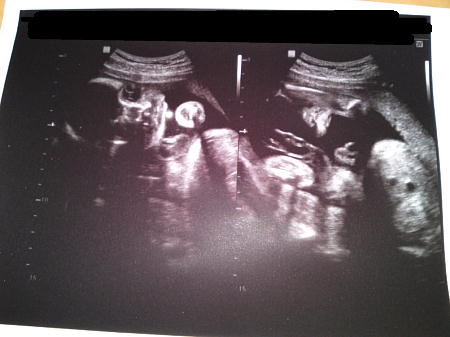

左側の写真は横向きかな?

頭、背骨がはっきりわかります。

右側は顔がこっちを向いています。

良く見ると目鼻口がわかります。

大地はこの写真を見て「ちょっと怖いね・・・(笑)」と言ってました。